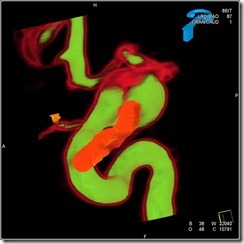

Case 3: Angiogram in a case of previously coiled Acom and left MCA aneurysms

2D DSA and 3D DSA run with volume rendering showing coiled left MCA and Acom aneurysms. There are contrast filled outpouchings seen at both locations again. However, it is difficult to evaluate the aneurysms, parent arteries and the coil mass inter-relationship. We do not know whether these are regrown aneurysms or new ones adjacent to the previously coiled ones.

Dual volume images show clearly that the MCA aneurysm has regrown and a fresh 'kissing’ aneurysm has come up at Acom adjacent to the previous one. clear visualisation of the parent artery, the arterial branches, aneurysm neck and the coil mass is apparent .